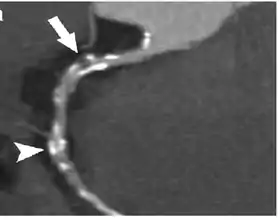

Coronary Computed Tomography Angiography (CCTA)

Computed tomography angiography (CTA), an imaging methodology using a ring-shaped machine with an X-Ray source spinning around the circular path so as to bathe the inner circle with a uniform and known X-Ray density. Cardiology uses are growing with the incredible developments in CT technology. Currently, multidetector CT, specially the 64 detector-CT are allowing to make cardiac studies in just a few seconds (less than 10 seconds, depending on the equipment and protocol used). These images are reconstructed using algorithms and software. Great development and growth will be seen in the short term, allowing radiologists to diagnose cardiac artery disease without anesthesia and in a non-invasive way.

Coronary CT calcium scan

A coronary CT calcium scan is a computed tomography (CT) scan of the heart for the assessment of severity of coronary artery disease. Specifically, it looks for calcium deposits in the coronary arteries that can narrow arteries and increase the risk of heart attack.[8] This severity can be presented as Agatston score or Coronary Artery Calcium (CAC) score. The CAC score is an independent marker of risk for cardiac events, cardiac mortality, and all-cause mortality.[9] In addition, it provides additional prognostic information to other cardiovascular risk markers.[9] A typical coronary CT calcium scan is done without the use of radiocontrast, but it can possibly be done from contrast-enhanced images as well, such as in coronary CT angiography.[10]